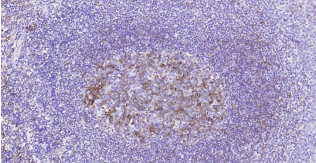

HLA-DR, like other MHC class II molecules, is a transmembrane glycoprotein composed of a 36 kDa alpha chain (DRA) and 27 kDa beta chain (DRB). The alpha chain gene contains 5 exons. Exon 1 encodes the leader peptide, exons 2 and 3 encode the two extracellular domains, and exon 4 encodes the transmembrane domain and the cytoplasmic tail. DRA does not have polymorphisms in the peptide binding part and acts as the sole alpha chain for DRB1, DRB3, DRB4 and DRB5. Within the DR molecule the beta chain contains all the polymorphisms specifying the peptide binding specificities. Hundreds of DRB1 alleles have been described and typing for these polymorphisms is routinely done for bone marrow and kidney transplantation. HLA-DR is expressed primarily on antigen presenting cells such as B lymphocytes, monocytes, macrophages, thymic epithelial cells and activated T lymphocytes. Three loci, DR, DQ and DP, encode the major expressed products of the human class II region. The human MHC class II molecules bind intracellularly processed peptides, present them to T-helper cells, and have a critical role in the initiation of the immune response.

| 12 | Control slide (Human spleen) | 1 slide | RTU | RT |